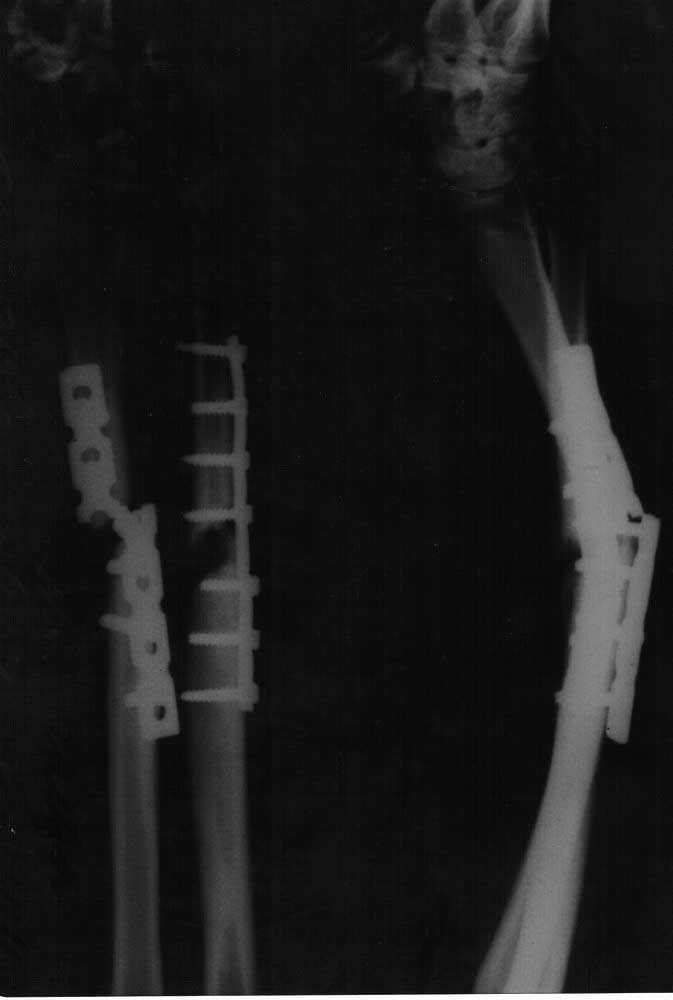

Активно курящая, умеренно пьющая, работающая на сомнительном, но производстве пациентка 37 лет. Заранее извиняюсь, но рентгенограмм предыдущих этапов лечения предоставить не могу (и вряд ли смогу в дальнейшем). Пациент из другого города. Первичная травма - закрытый перелом 22 - В3. Далее МОС (5 мес назад), результат которого Вы видите. Местно - кисть отечна, но безболезненна. Движения (кроме ротационных) - незначитлеьно ограничены. Рубцы без грубого воспаления, хотя отек и гиперемия есть. Вопрос - как делать? В выборе имплантов крайне ограничены, сама ничего интересного не потянет. Нам считается предпочтительным (после того как все убрать и освежить) - укоротить, перевести в простые поперечные переломы и максимально стабильно синтезировать (пластинами)(с какой начать? насколько укоротить?). Попутно вопрос по головке локтевой... Еще раз извиняюсь - пока снимки только такого качества и укладок.